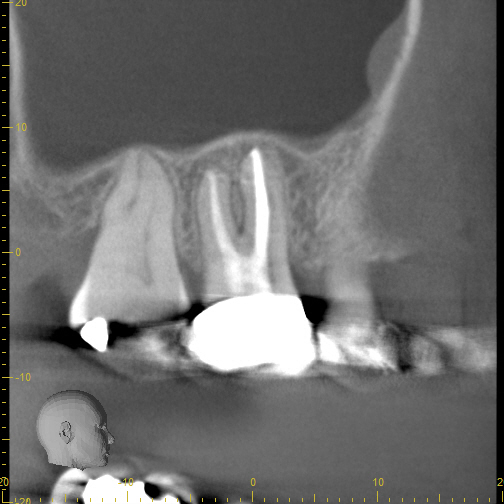

Case 5

Another case showing dramatic healing from root canal treatment. This patient had chronic sinus inflammation that never seemed to heal. The cause--an infected tooth. The top row images show both an erosion of the sinus floor from the tooth roots into the sinus cavity, as well as significant inflammation (swelling) of the sinus soft tissues that line the sinus. During retreatment I was able to find and clean all the canals, including one canal that was previously missed during the first root canal (I did not treat the original root canal). The bottom row images (one year later) shows complete re-establishment of the sinus floor (the bone that separates the sinus from the teeth) and complete resolution of the sinus swelling. There is no more infection. This retreatment case shows that even if a root canal treatment has failed, it can still often be saved. Always seek evaluation from an Endodontist before pulling out a "failing root canal"!